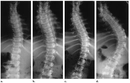

Cervikal OmurgaCervikal omurga, boyun bölgesinde bulunan yedi omurdan oluşmaktadır (C1-C7). Bu bölge, başın hareketini ve başın ağırlığını dengelemeye yardımcı olur. Özellikle C1 ve C2 omurları, başın dönmesini sağlayan özel yapılar içerir. Cervikal omurgada meydana gelen herhangi bir yaralanma ya da dejenerasyon, baş dönmesi ve sinir kökü sıkışması gibi klinik durumlardan kaynaklanan semptomlara yol açabilir. Thorakal OmurgaThorakal omurga, on iki omurdan (T1-T12) oluşur ve göğüs kafesini destekler. Bu bölgedeki omurlar, kaburgalarla bağlantılıdır ve bu nedenle göğüs boşluğunun stabilitesine katkı sağlar. Thorakal omurgada meydana gelen deformiteler, genellikle kifoz veya skolioz gibi duruş bozukluklarına yol açabilir. Lumbar OmurgaLumbar omurga, bel bölgesinde bulunan beş omurdan (L1-L5) oluşur. Bu bölge, vücut ağırlığını destekler ve hareketliliği artırır. Lomber omurga, en sık yaralanma ve dejenerasyon geçiren bölgedir. Lomber disk herniasyonu, bel ağrısı ve siyatik gibi problemlerle ilişkilidir. Sakral OmurgaSakral omurga, beş birleşik omurdan (S1-S5) oluşur ve pelvis ile bağlantılıdır. Bu bölge, vücudun alt kısmına destek sağlar ve hareketliliği azaltır. Sakral omurga, doğum sırasında önemli bir rol oynar ve sakral ağrı gibi klinik durumlarla ilişkilendirilebilir. Omurga Çeşitlerinin Ayırt EdilmesiOmurga çeşitlerinin ayırt edilmesi, aşağıdaki yöntemler kullanılarak gerçekleştirilir: